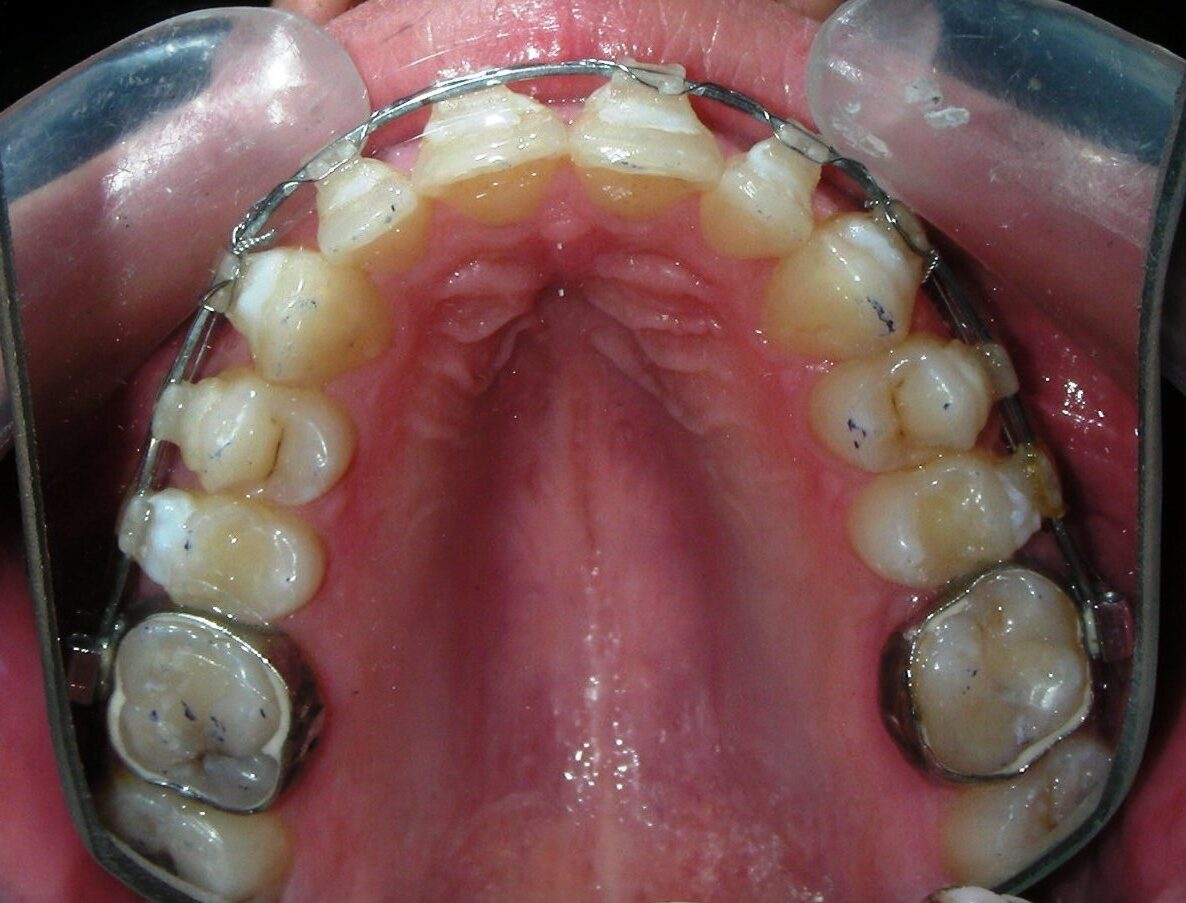

Was installed a Hyrax-type 10mm palatal expander of the Brazilian trademark Morelli® , modified by the author to be adapted to receive TADs microscrews, in order to initiate maxillary disjunction with MARPE (Mini-implant Assisted Rapid Palatal Expansion), TADS was installed with skeletal anchorage placed bilaterally having as references the roots of the maxillary canines and first premolars. Prior to insertion, local infiltrative anesthesia was administered using 2% lidocaine hydrochloride with 1:100,000 epinephrine. A total dose of approximately 0,8 mL per side (cortical infiltration technique). The TADs were inserted under aseptic conditions using a manual driver. Microscrew Evolution 1,6 Ø x 10 mm from the Argentine brand Odontit® . The Hyrax expander was then fitted and activated after 48 hrs .

Protocol of one activation per day was followed for a period of three weeks where the first clinical and radiographic evaluation was performed, showing clear signs of skeletal expansion, including the presence of a midline diastema. One more week of activations was added with a total of 28. The patient reported moderate headache during the first week of activation.

Having successfully achieved the expansion, we proceed to the intrusion of the posterior superior sectors, modifying the Hyrax by adding anchoring hooks at the buccal level of the first premolars. Using the Hyrax as anchorage, we sought a parallel intrusion. This could be replaced by a palatal bar. TADs were installed bilaterally at the mesial level of the first molars, inserting them as parallel as possible to the roots.

Simultaneously we begin with the alignment of the lower arch ,Simultaneously we began with the alignment of the lower arch with Roth prescription ceramic braces .022 . Henry Schein®

As the reader may infer, alignment and leveling of the upper anterior segment are being intentionally deferred at this stage of treatment. This strategic decision is based on the primary objective of closing the anterior open bite not through anterior extrusion, but by means of controlled posterior intrusion. This biomechanical approach promotes a counterclockwise rotation of the mandible, which leads to a increase in the facial axis angle and improvement in vertical facial proportions. By avoiding early anterior alignment, we prevent any premature vertical displacement of the upper incisors.